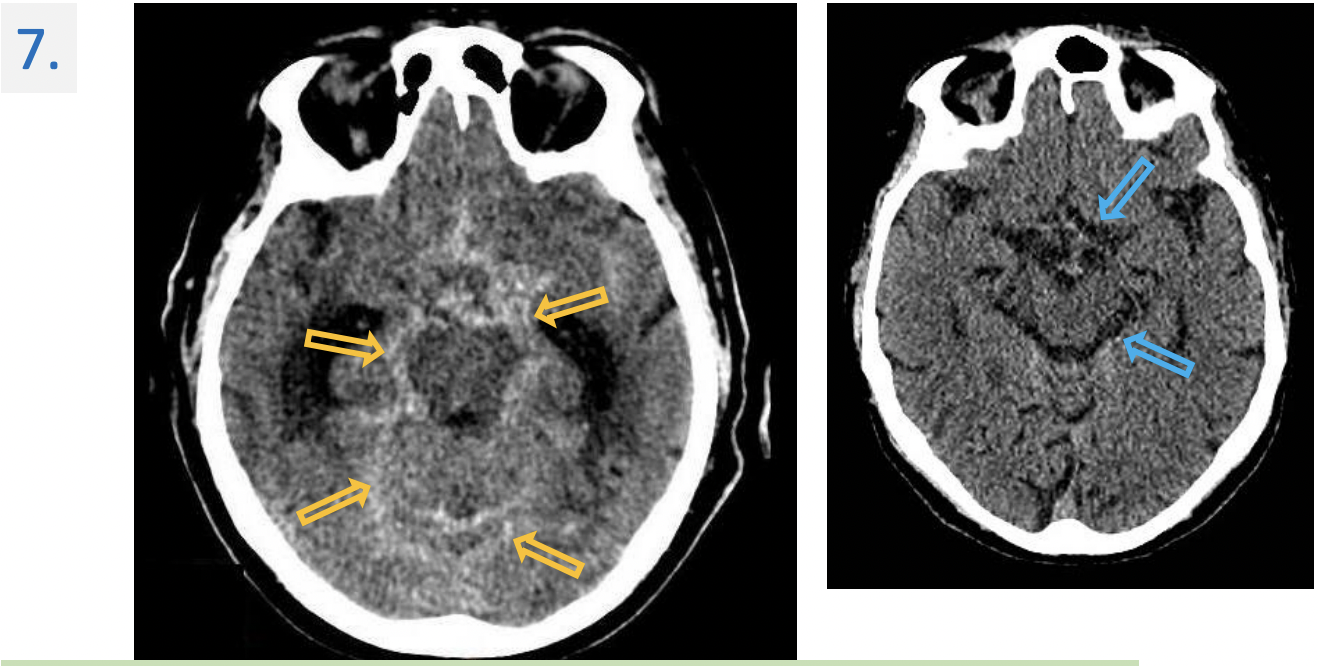

7.